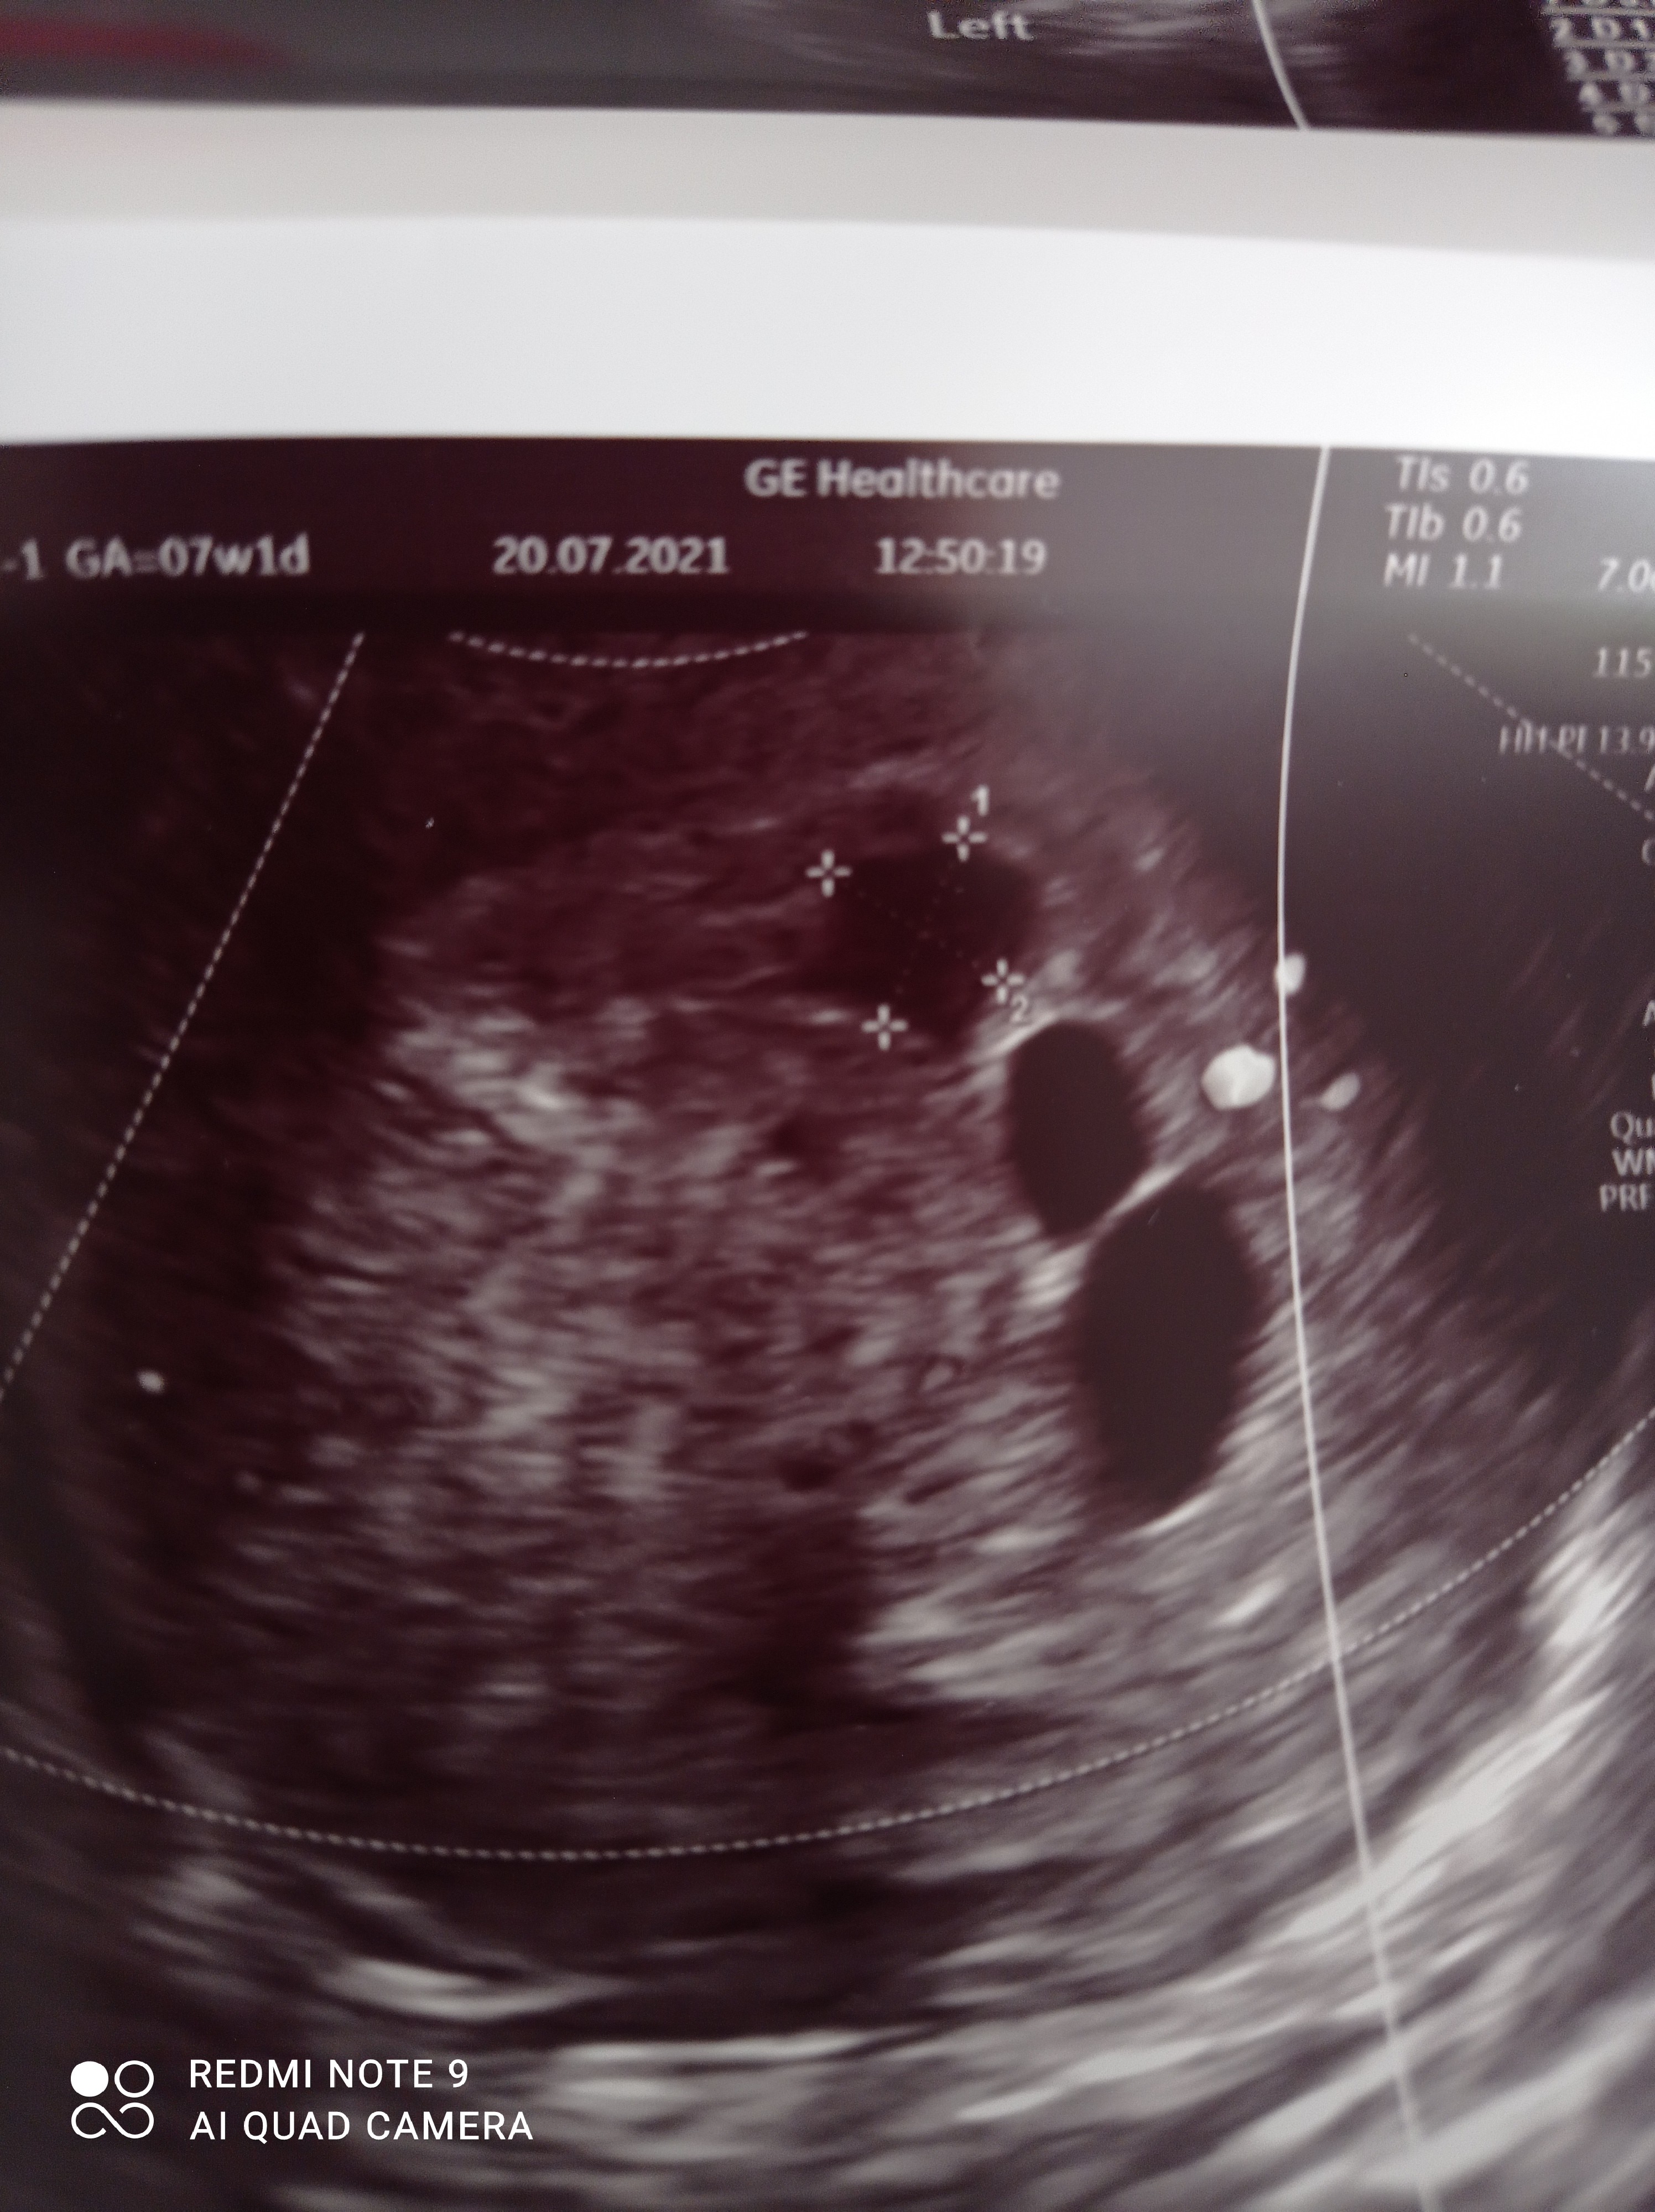

Widzę, że jedziemy na tym samym wózku. Oby w piątek się coś u Ciebie pokazało. Trzymam mocno za Ciebie kciukiJestem już po wizycie. Tak jak przypuszczałam, nadal puste pęcherzelekarz kazał czekać tydzień i jeszcze raz na wizytę i zlecił bhcg, dzisiaj mają być wyniki. Dzisiaj jestem 7+0 wg usg ostatniego. To był lekarz na nfz. W piątek jestem jeszcze umówiona do swojego lekarza prywatnie, może znowu stanie się cud i zarodek się pokaże.

Pęcherzyk jeden ma 15 mm, a drugi 8mm.

kiedy robisz betę?Jestem już po wizycie. Tak jak przypuszczałam, nadal puste pęcherzelekarz kazał czekać tydzień i jeszcze raz na wizytę i zlecił bhcg, dzisiaj mają być wyniki. Dzisiaj jestem 7+0 wg usg ostatniego. To był lekarz na nfz. W piątek jestem jeszcze umówiona do swojego lekarza prywatnie, może znowu stanie się cud i zarodek się pokaże.

Trzymam kciuki za piątkowa wizytę ❤ Jak prywatnie, to wiele się może zmienić jak wiemy w tym obrazie usg. Daj znać jak dzisiejsza betaJestem już po wizycie. Tak jak przypuszczałam, nadal puste pęcherzelekarz kazał czekać tydzień i jeszcze raz na wizytę i zlecił bhcg, dzisiaj mają być wyniki. Dzisiaj jestem 7+0 wg usg ostatniego. To był lekarz na nfz. W piątek jestem jeszcze umówiona do swojego lekarza prywatnie, może znowu stanie się cud i zarodek się pokaże.